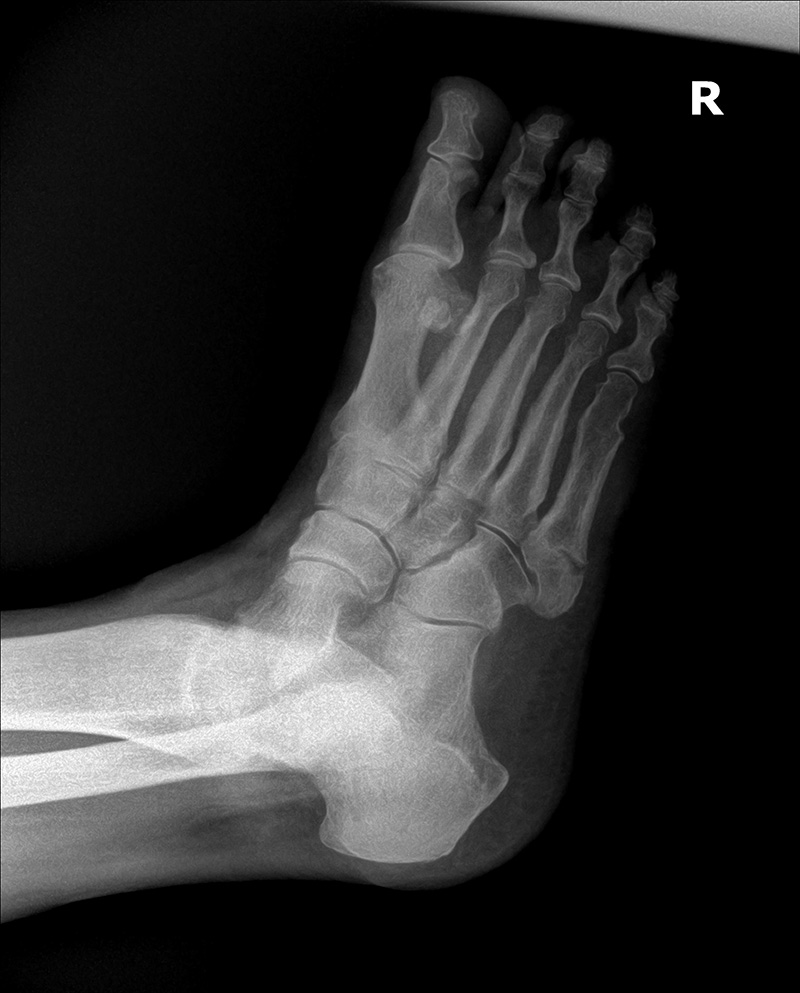

Initial Oblique view to post 4 week oblique view